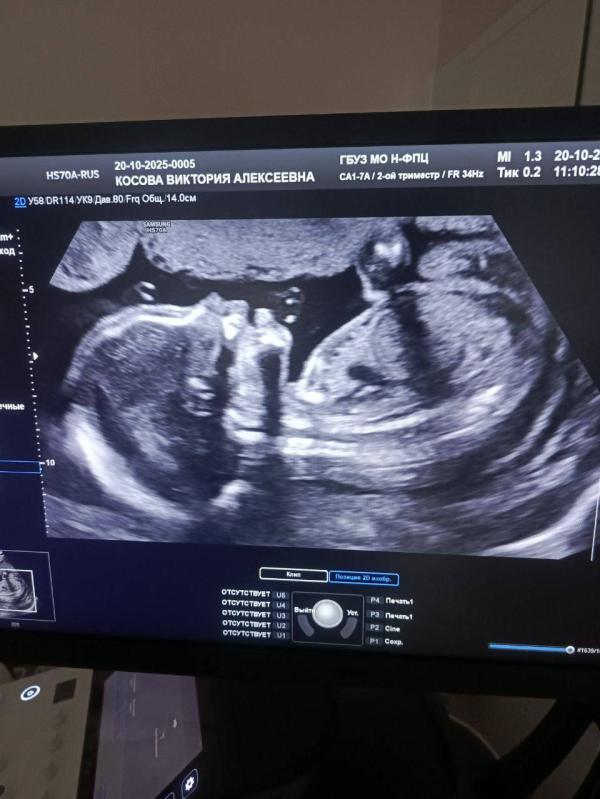

Ну что ж 2 скрининг пройден . Я так переживала как будто впервые беременна . Но все хорошо , развиты по сроку , отклонений нету . Забрала кровь первого скрининга у меня впервые за все беременности ни одного показателя ниже 1 к 900 нету , ато и до тысяч риски доходят . Сказать что я рада это ничего не сказать ☺️. А как прошел ваш 2 скрининг ? Как самочувствие во 2 триместре ?